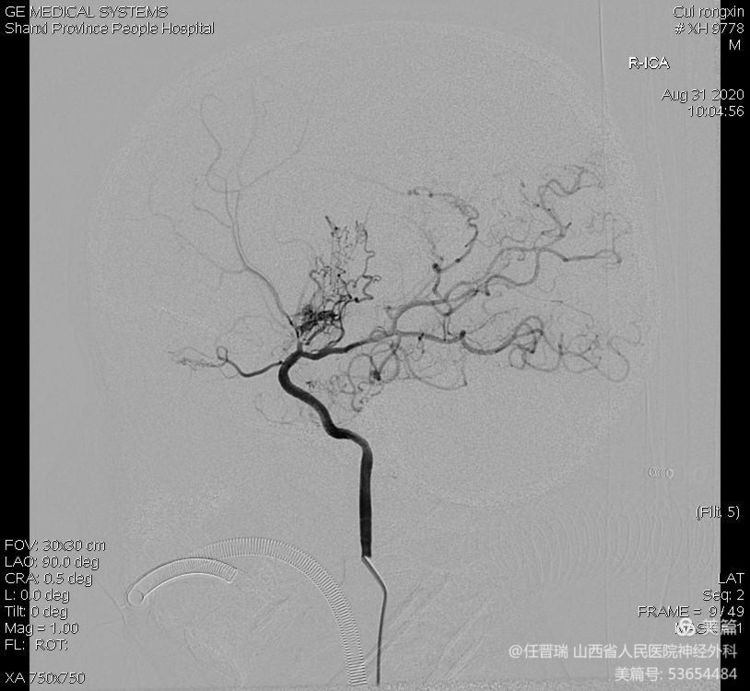

全脑血管造影:双侧大脑中动脉及双侧大脑前动脉闭塞,颈内动脉末端烟雾样血管形成